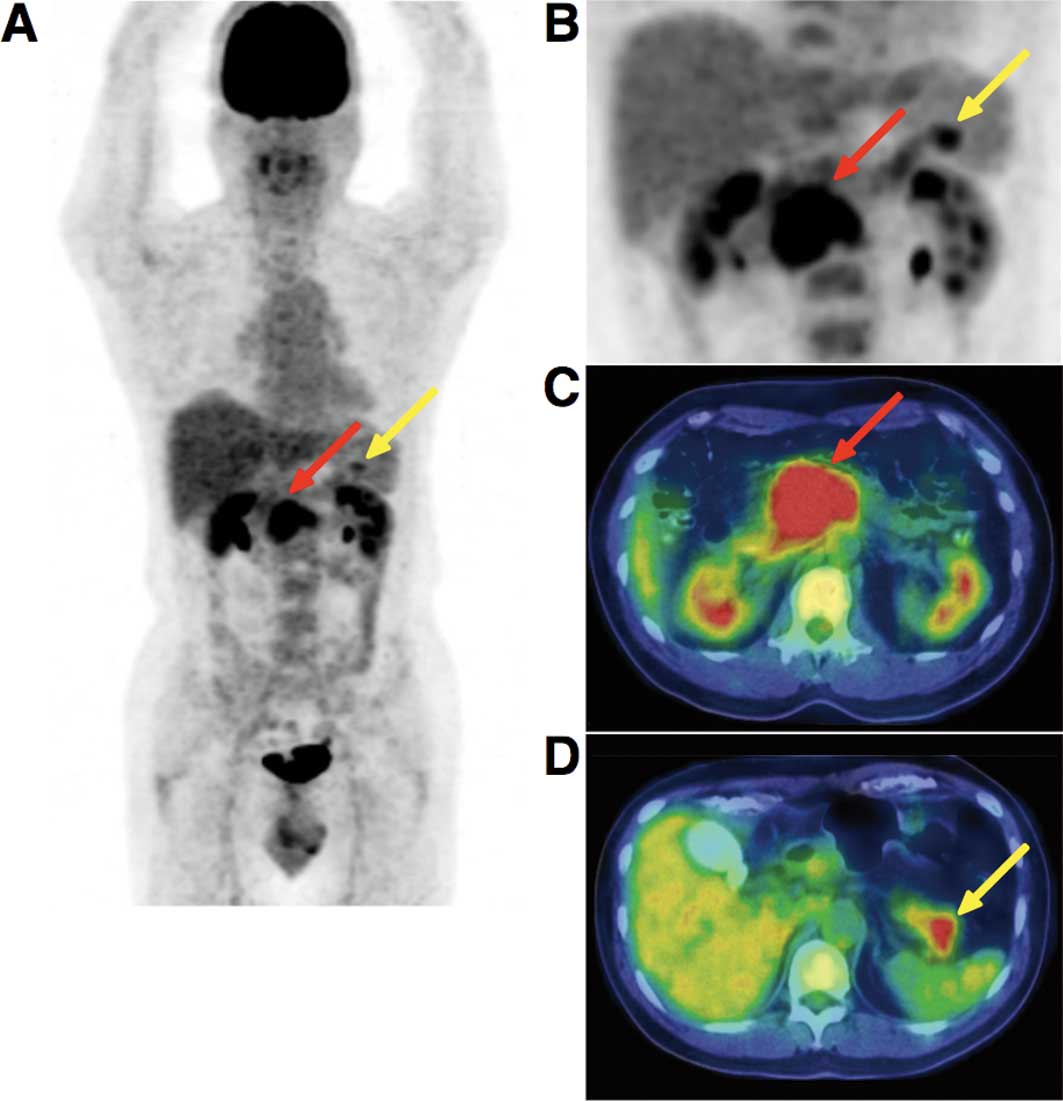

Suv в пэт-кт рак молочной железы - фото презентация